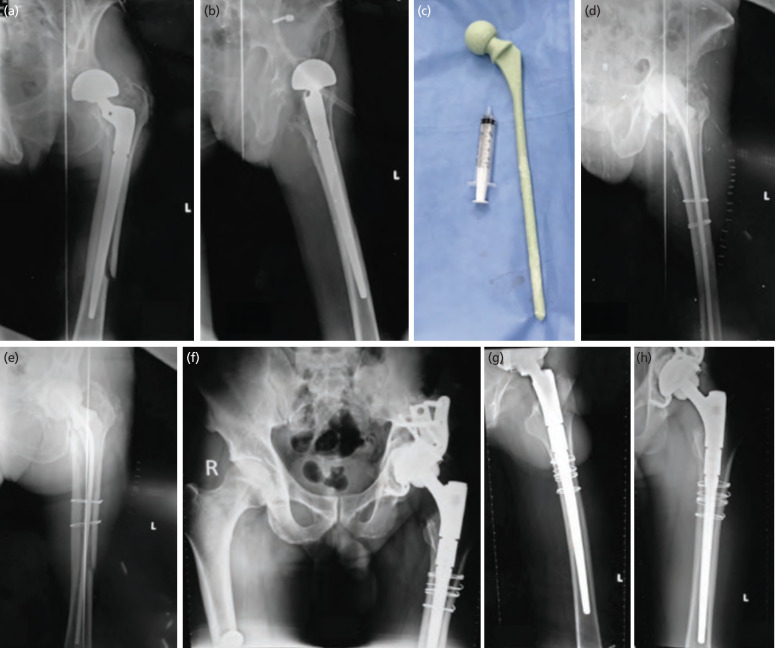

Introduction: Periprosthetic joint infection combined with periprosthetic fracture rarely occurs simultaneously. Once all components of the periprosthetic joint infection were removed, antibiotic spacers were placed. Moreover, periprosthetic fractures require fixing. We use a long femoral stem spacer molded intra-operatively via a self-design metal mold as a novel treatment method for the periprosthetic fracture combined with infection.

Material and methods: The study reviewed 12 patients who underwent two-stage revision arthroplasty with long femoral stem spacers over 6 years. During a minimum of two years of follow-up, the outcomes were evaluated, including reinfection rates, reimplantation rates, and re-operation rates, as well as the success rate based on the MSIS criteria.

Results: Twelve patients underwent two-stage revision with a long femoral stem spacer between stages. A mean follow-up period of 9.58 months followed infection (range 2 to 28 months). In 11 patients (91.67%), the infection was eradicated. There was one patient (8.33%) who required a second 2-stage revision and subsequently cleared their infection. The long femoral stem spacer was repeated in three patients (25%). After eradicating the infection, 9 patients (75%) underwent 2nd stage revision, on average 8.56 months after the first stage. At an average of 27.92 months (range 8 - 65 months) post-operatively, three (25%) long femoral stem spacers remained in place.

Conclusion: Using long femoral stem spacers, both periprosthetic joint infections and periprosthetic fractures can be treated simultaneously. In the cases with multiple organisms, we mixed one pack of bone cement with 2g of Vancomycin and 2g of Meropenem, resulting in satisfactory results.